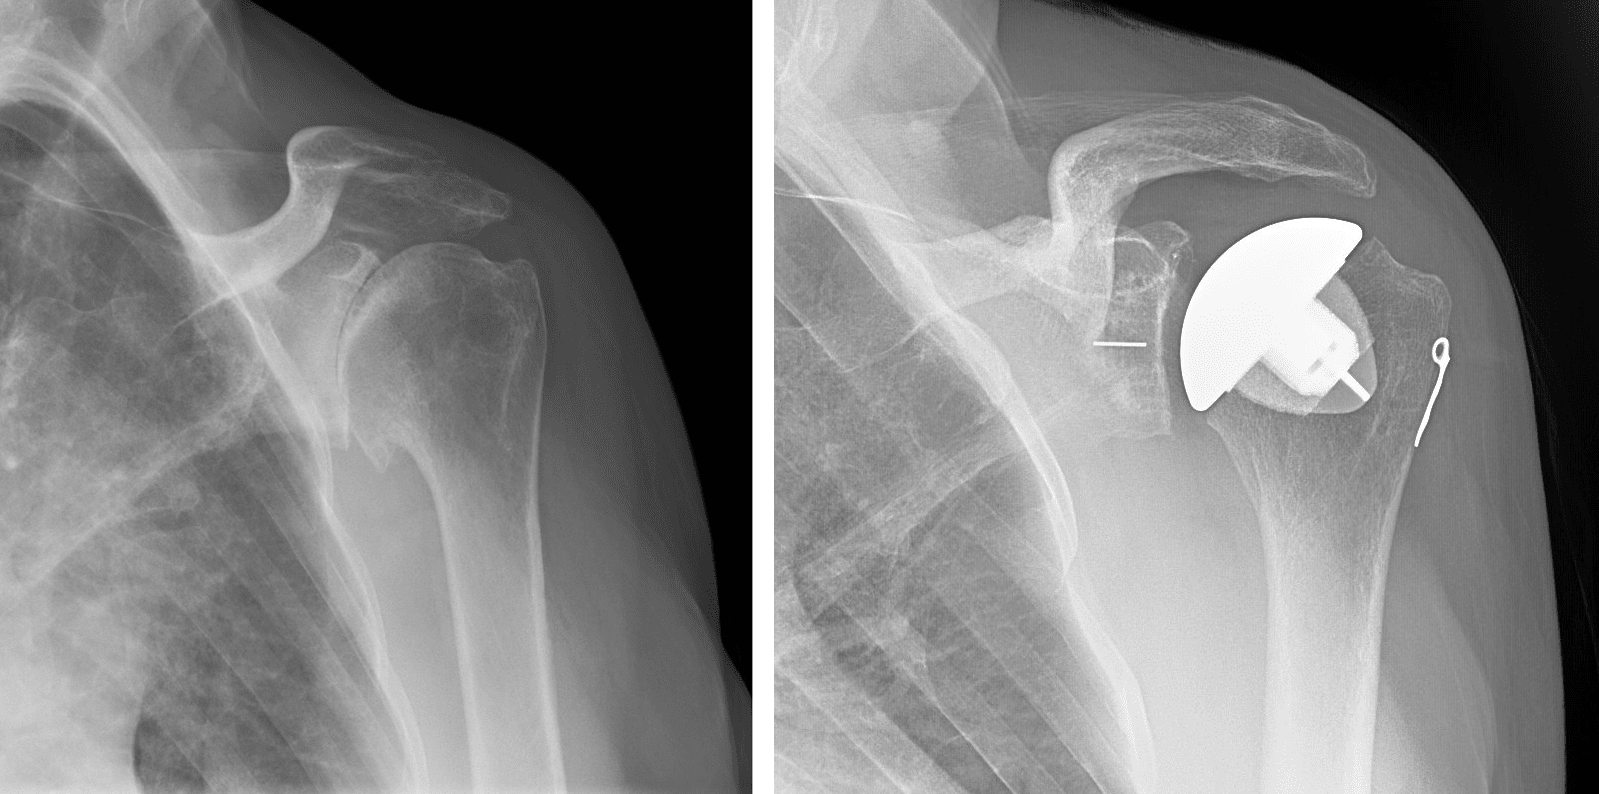

Shoulder

Replacement

Innovative shoulder replacement solutions for pain relief and restored motion.

Resurfacing Shoulder Arthroplasty

Minimally invasive resurfacing for early-stage shoulder arthritis and joint damage.